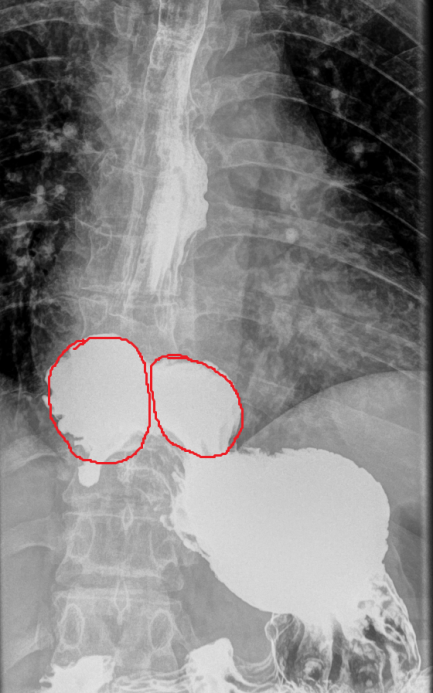

Different views of a double contrast-enhanced CT scan showing a left diaphragmatic hernia with an acute dilated stomach (Courtesy Dr. V. Penopoulos)